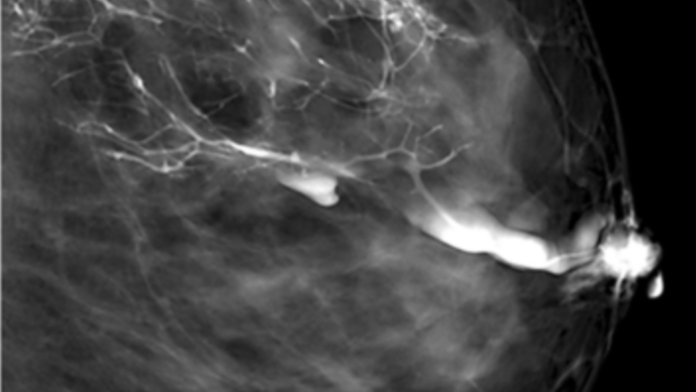

Mit der Untersuchung können Ärztinnen und Ärzte also einen Teil des Milchgangsystems sichtbar machen. Dies ist mithilfe einer einfachen Mammographie nicht möglich, da sich die Milchgänge in ihrer Dichte nicht vom umgebenden Bindegewebe unterscheiden und daher im Röntgenbild normalerweise nicht zu erkennen sind.

Im Anschluss an die Kontrastmittelinjektion folgt eine Mammographie. Durch das Kontrastmittel wird der Verlauf des Milchgangs in den Mammographie-Aufnahmen sichtbar. Fachleute können so erkennen, ob er durch einen gutartigen oder bösartigen Tumor eingeengt oder blockiert ist.

Bildhinweis: Das Copyright des Bildes "Ein Teil des Milchgangsystems der Brust erscheint durch die Galaktographie in einer Mammographie-Aufnahme intensiv weiß." liegt bei M. Moschetta et al., Wikimedia Commons unter der Lizenz CC BY-SA 3.0.